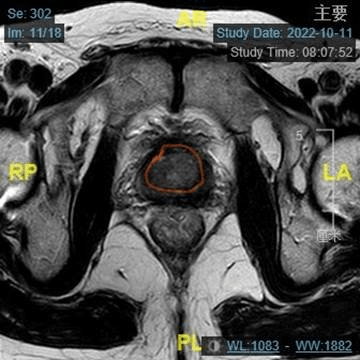

出院后杨大爷定期使用新辅助内分泌治疗,3个月后再次到我院就诊,复查TPSA及前列腺MRI,TPSA降至0.06ng/mL,游离PSA/总PSA为0.32,前列腺MRI提示病变与3个月前比较,病变范围缩小,前列腺大小约18g,与3个月前相比明显缩小。王春阳主任认为杨大爷现在行手术治疗,术后效果能达到预期。

王春阳主任团队制定了周密的手术方案,采用已经成熟开展的Hood及单孔机器人技术,在各方的配合下手术从麻醉开始至结束历时3.5个小时后得以顺利完成,术中出血量仅20ml,术后第二天查房时患者已排气,可以正常吃饭,术后5天顺利出院。术后病理回报提示:前列腺腺癌,Gleason评分4+4。